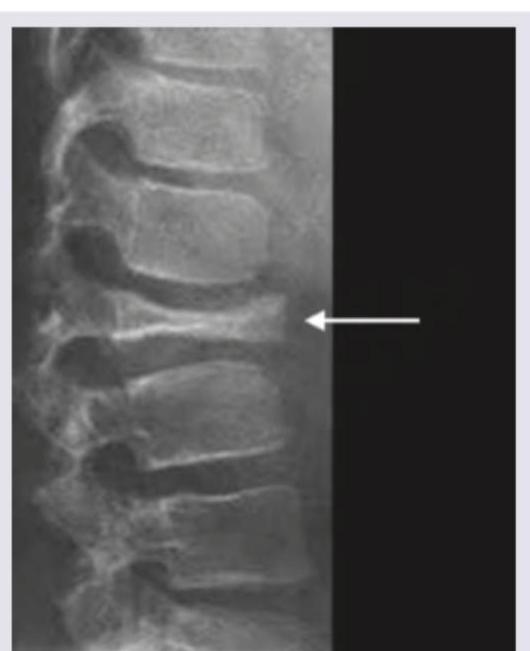

A 56-year-old female presents with chronic lower back pain. A lateral lumbar spine X-ray is provided. Based on the radiological findings, which of the following is the most likely diagnosis?

Explanation: ***Fish vertebra*** - The image shows **biconcave vertebral body deformities** (marked by the arrow), where both the superior and inferior endplates are collapsed centrally, resembling the shape of a fish vertebra. - This appearance is typically seen in conditions like **severe osteoporosis** or metabolic bone diseases (e.g., **osteomalacia**). *Osteoporotic spine* - While **osteoporosis can lead to fractures and vertebral body collapse**, "osteoporotic spine" is a broader diagnosis. - The specific pattern of **biconcave collapse** seen here is more precisely described as fish vertebra, often a consequence of severe osteoporosis. *Anterior beaking vertebra* - **Anterior beaking** refers to a localized projection or pointed anterior vertebral body, often seen in conditions like mucopolysaccharidoses or trauma. - This is distinct from the **central biconcave collapse** visible in the provided image. *Vertebra plana* - **Vertebra plana** describes a vertebral body that has **uniformly collapsed in height**, making it very flat. - The image shows a **biconcave deformity** with central compression, not a uniform flattening of the entire vertebral body.